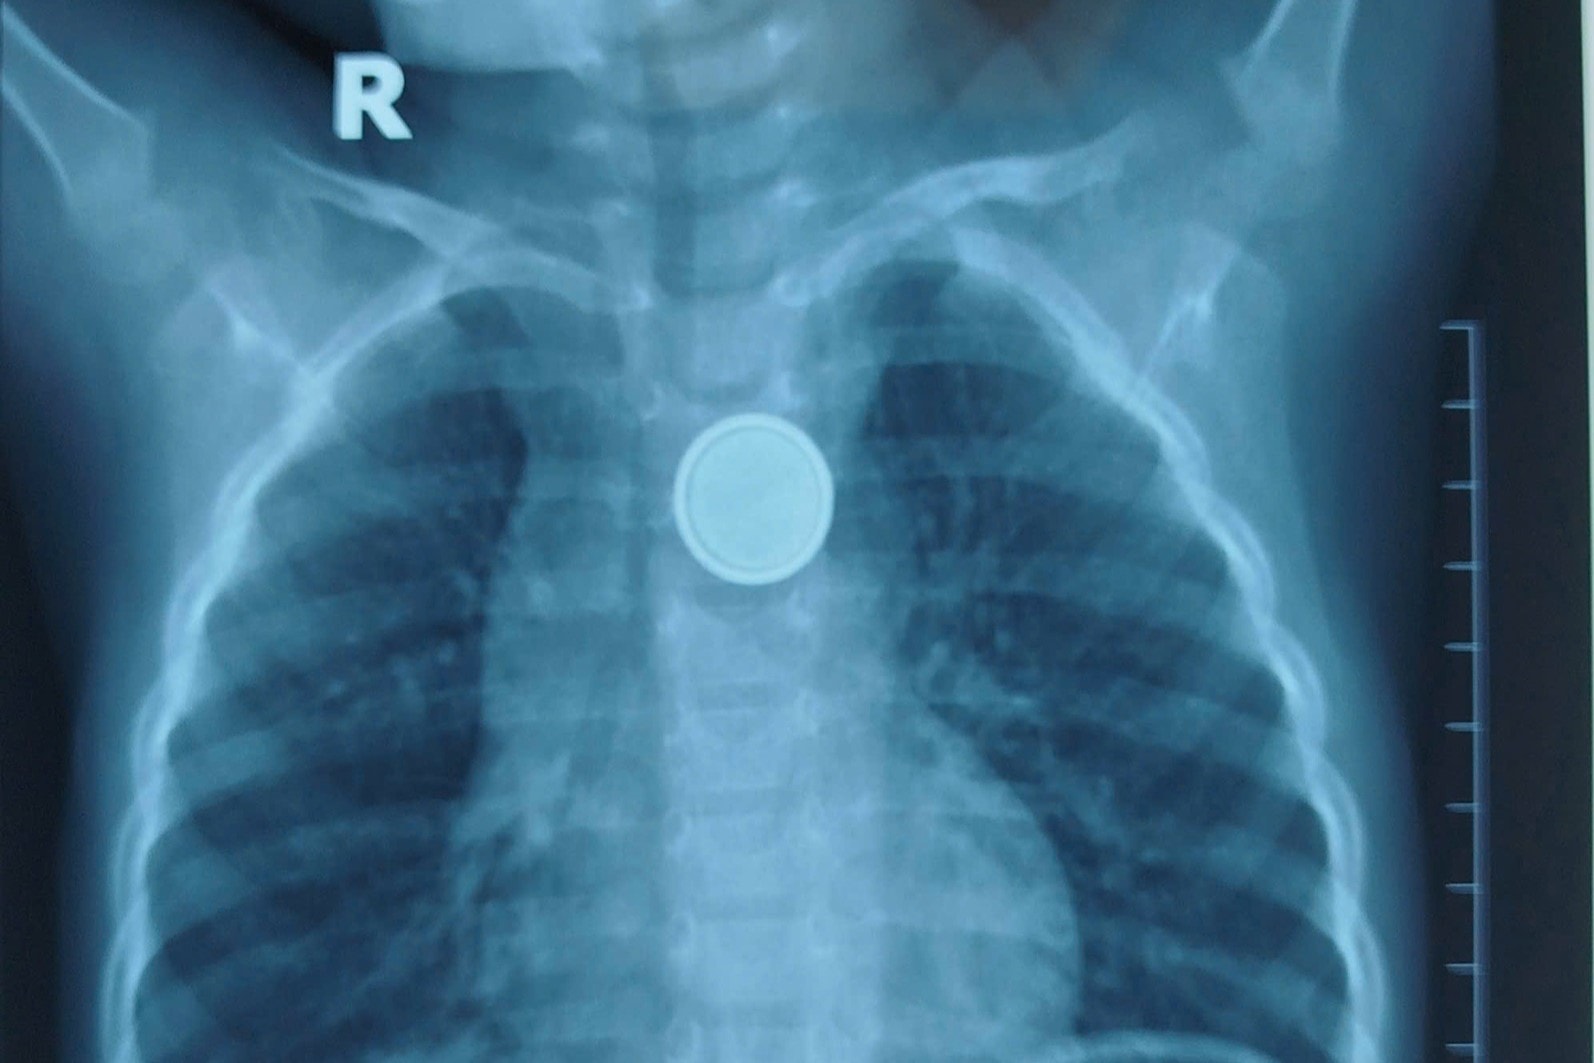

Kết quả X-quang xác định pin mắc tại thực quản. Trong ca nội soi cấp cứu, bác sĩ gắp ra thành công nhưng ghi nhận vùng tổn thương loét rộng do pin gây ăn mòn nhanh, cho thấy mức độ nguy hiểm ngay cả khi trẻ được tiếp cận y tế sớm.

Dị vật là pin cúc áo trong thực quản trẻ khi được chụp X-quang. Ảnh: BVCC